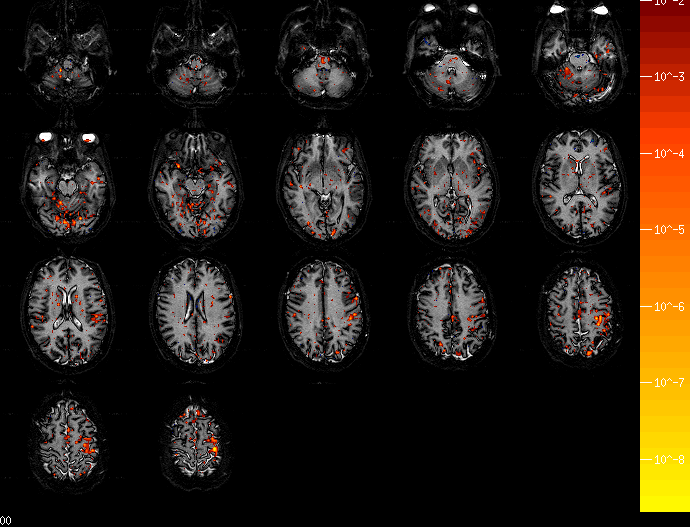

• Nestor's Brain Tracking a Motor Sequence w/o Prior Info ,

various horizontal slices.

• Nestor's Brain Tracking a Motor Sequence with Prior Info ,

• Nestor's Brain During "Practeach" Condition in Gary's Experiment ,